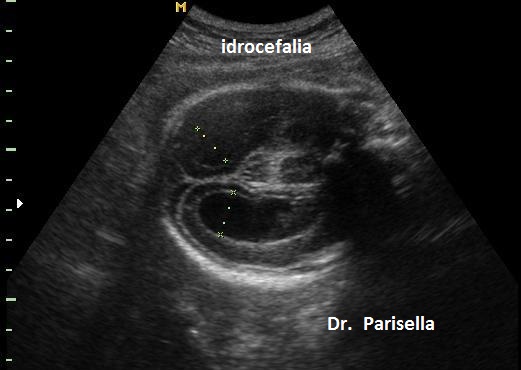

Le anomalie facciali consistono in labiopalatoschisi e micrognazia. Le anomalie degli arti consistono in ipoplasia delle falangi distali. Le anomalie cerebrali comprendono l'agenesia del corpo calloso e l'idrocefalia.